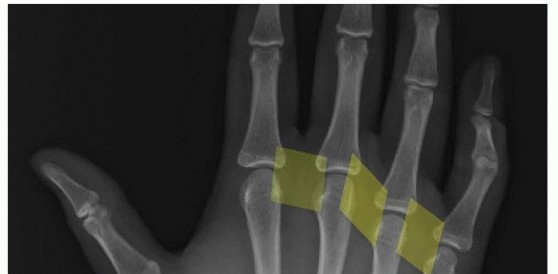

20 MIN READ Arthroscopic and Open Primary Repair of Acute Thumb Metacarpophalangeal Joint Radial and Ulnar Collateral Ligament Disruptions يناير 2023 Read More